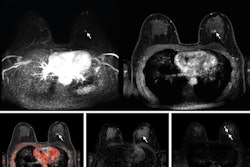

All exams were performed on a 3-tesla MRI scanner using dedicated breast coils with patients in the prone position; 7.5 ml of intravenous gadobutrol (1 mmol/ml) was administered during the exam.

The final diagnoses were obtained from the surgical reports and are shown below.